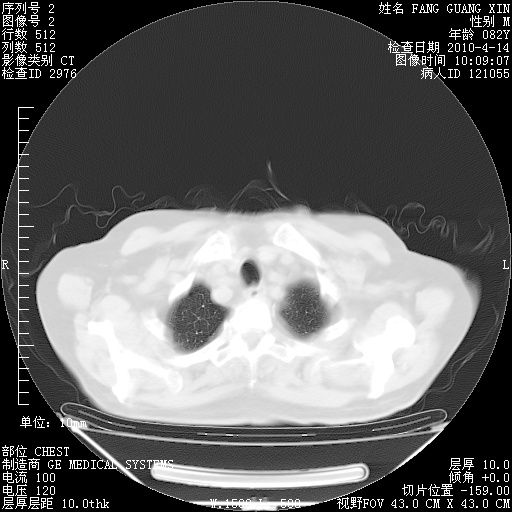

4月14日肺部CT